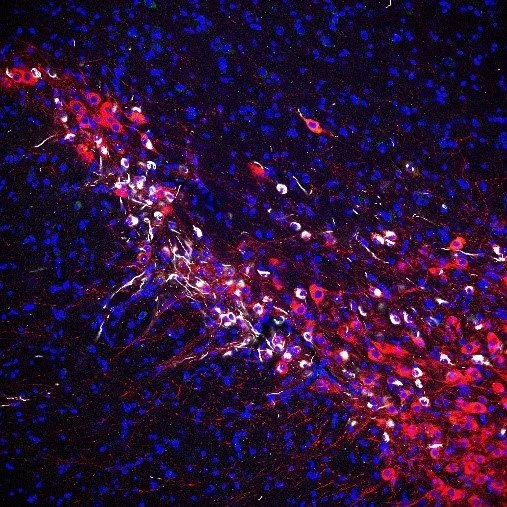

Parkinson’s disease is the most prevalent neurodegenerative movement disorder affecting millions of people worldwide. Neuropathologically, Parkinson’s disease is characterized by widespread loss of certain vulnerable neuronal populations, especially dopaminergic substantia nigra neurons, and formation of intraneuronal eosinophilic inclusions which stain positive for α-synuclein and are termed Lewy pathology.

Manifesting α-synuclein pathology (white) in dopaminergic substantia nigra neurons (red).